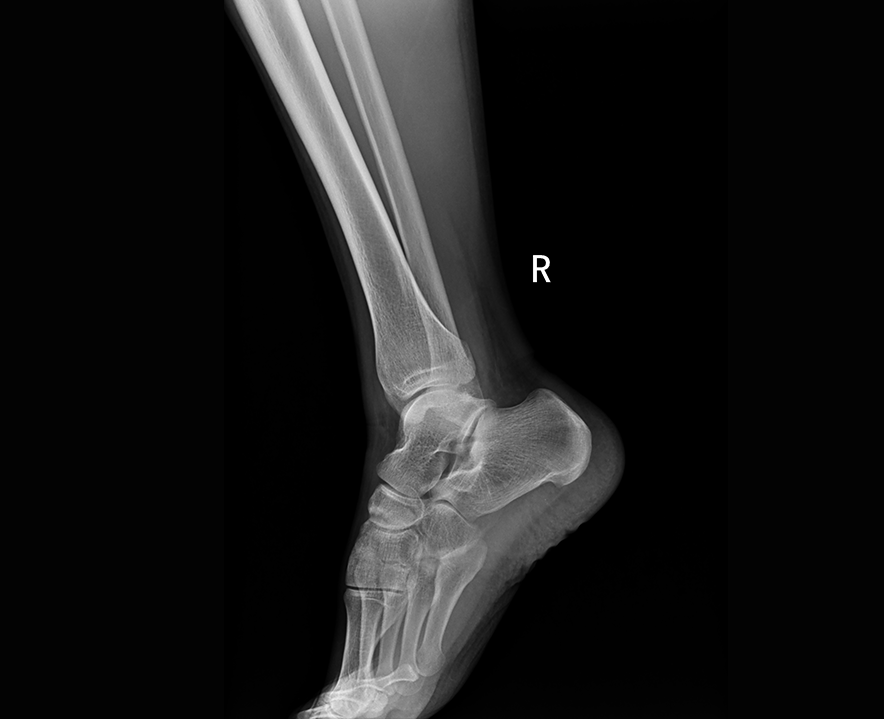

全球首臺 全三維骨關節與A測量負重錐束CT

自主研發高頻逆變高壓發生器,配合高效自主增強圖像處理技術,呈現清晰細膩的圖像效果。